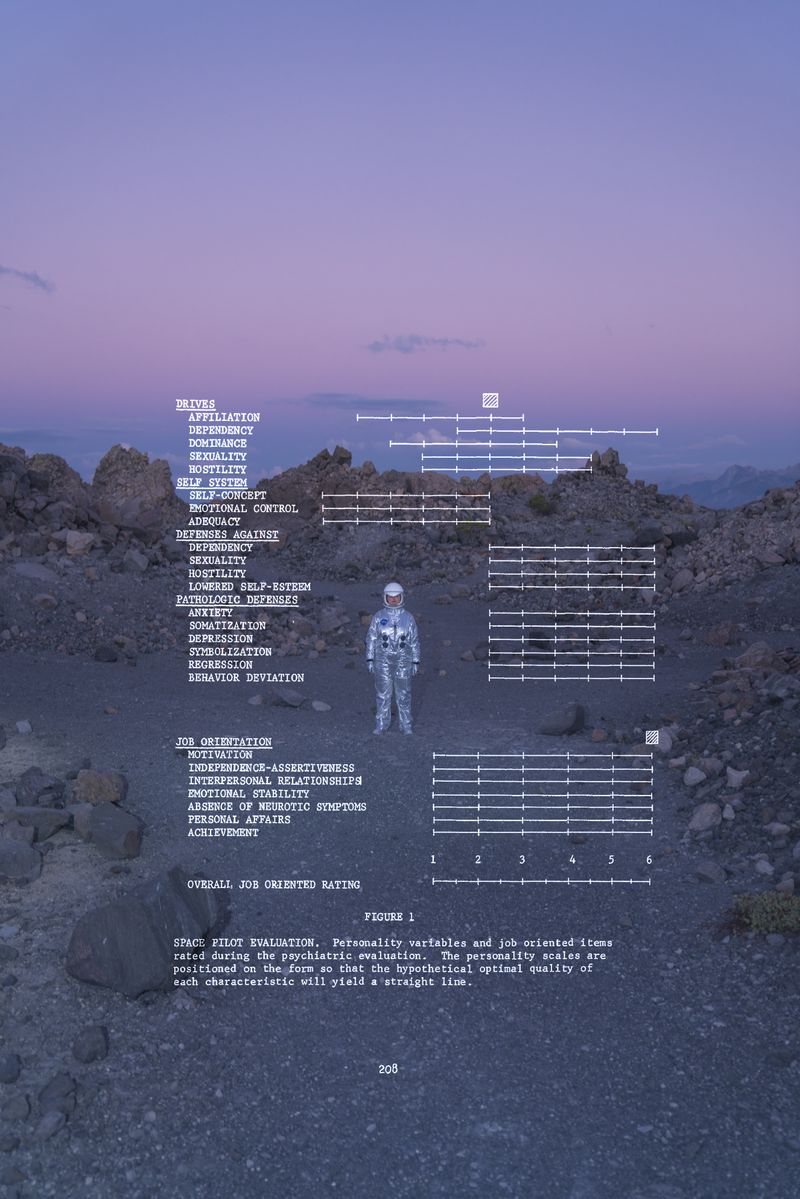

“When the inkblots came up, we looked at them and, sure enough, we’d always see some feminine anatomy in there to make sure that we gave the proper sexual response.” Jim Lovell, an astronaut in the Gemini and Apollo programs, recounts one of two mandatory heterosexuality tests that early NASA astronauts were required to take.

To date, 600 people have been astronauts. None have flown into space as an openly LGBTQ+ person.

The Gay Space Agency confronts the American Space program’s historical exclusion of openly queer astronauts and asks what American heroism looks like and who might be a part of future exploration. Reckoning with this history, the project uses archival images, current images of the space program, and surreal boundary-breaking photos to reimagine a history which celebrates queerness and highlights LGBTQ+ role models.

Today, NASA is joined by privately owned, billionaire-backed organizations in their exploration of the final frontier. As we revisit the possibilities of human expansion and future colonization, The Gay Space Agency asks what it means to have the "right stuff."